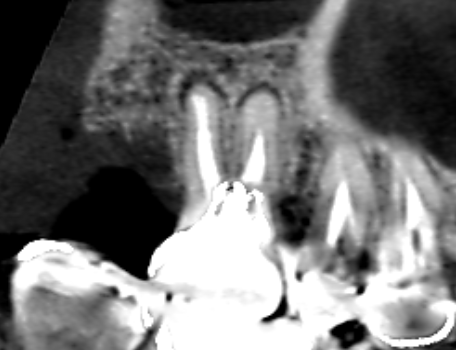

上顎第一大臼歯の頬側2根の矢状断のCT画像です。

上顎第一大臼歯の頬側2根共に根の先に小さい膿の影がみられます。